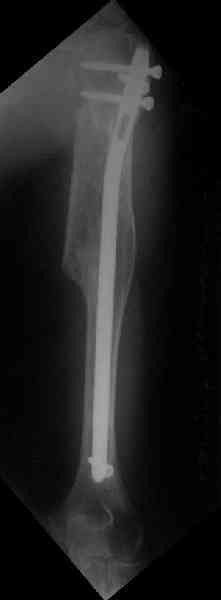

Здесь нет необходимости в серкляже. Вмешиваться на промежуточных отломках приходится, если есть угроза перфорации кожи, или промежуточный отломок попал в фасцию, как пуговица в петлю. В приложении сегментарный оскольчатый перелом плеча в проксимальном отделе, фиксированный больщеберцовым стержнем. Как видите, обошлось без серкляжа. Функция полная.

Пример отличный.

Вот что значит лечить перелом, а не рентгенограмму!

Александр, великолепные снимки! Вопрос - что за гвоздь?

Это укороченный большеберцовый стержень, которые делает предприятие "ЦИТО".

на синтезовский UTN похож))

Скажите пожалуйста, Александр Николаевич, почему Вы использовали большеберцовый гвоздь?

Доступные на тот момент гвозди для плеча имели худшие возможности фиксации в коротком проксимальном отломке.

Уважаемый Александр Николаевич! На продемонстрированных вами рентгенограммах имеется достаточно большое на мой взгляд смещение отломков после фиксации блокируемым гвоздем. На счет полной функции все понятно, а нет ли каких либо сосудистых расстройств конечности? Имею ввиду венозную недостаточность или лимфостаз.